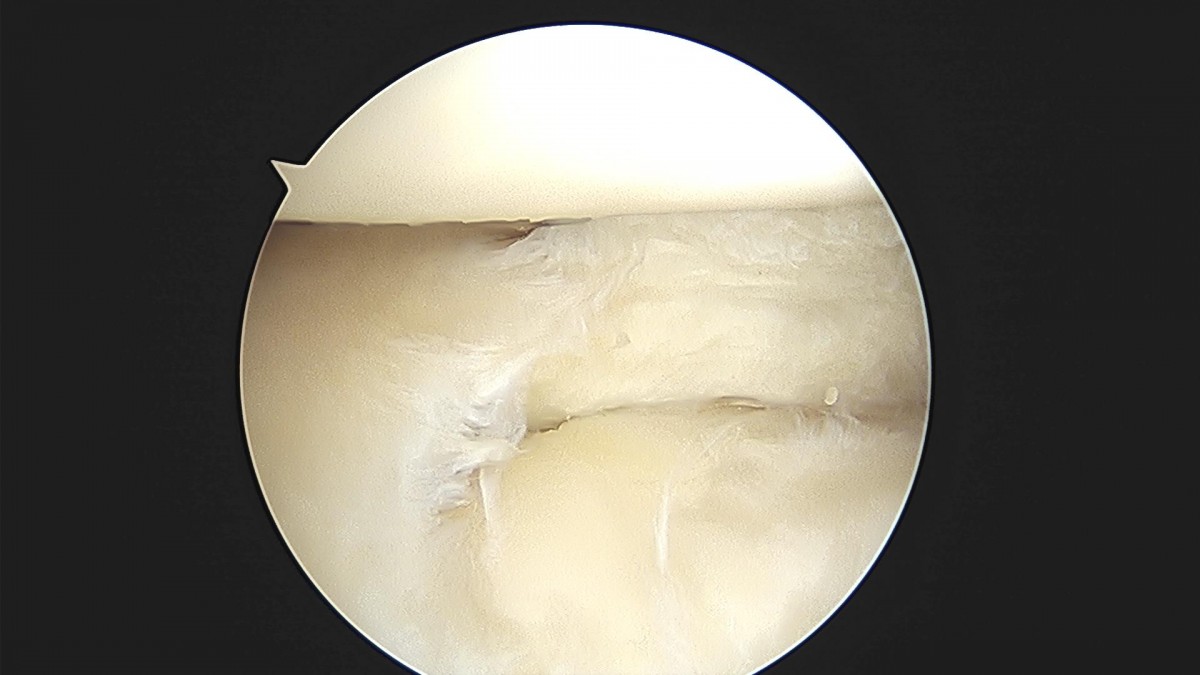

배우한원장님 무릎 내측 반월상 연골판 절제술 김도O 환자

bccafb0c4c611c3a9fcb6ca752df8d40_1670487534_138.jpg